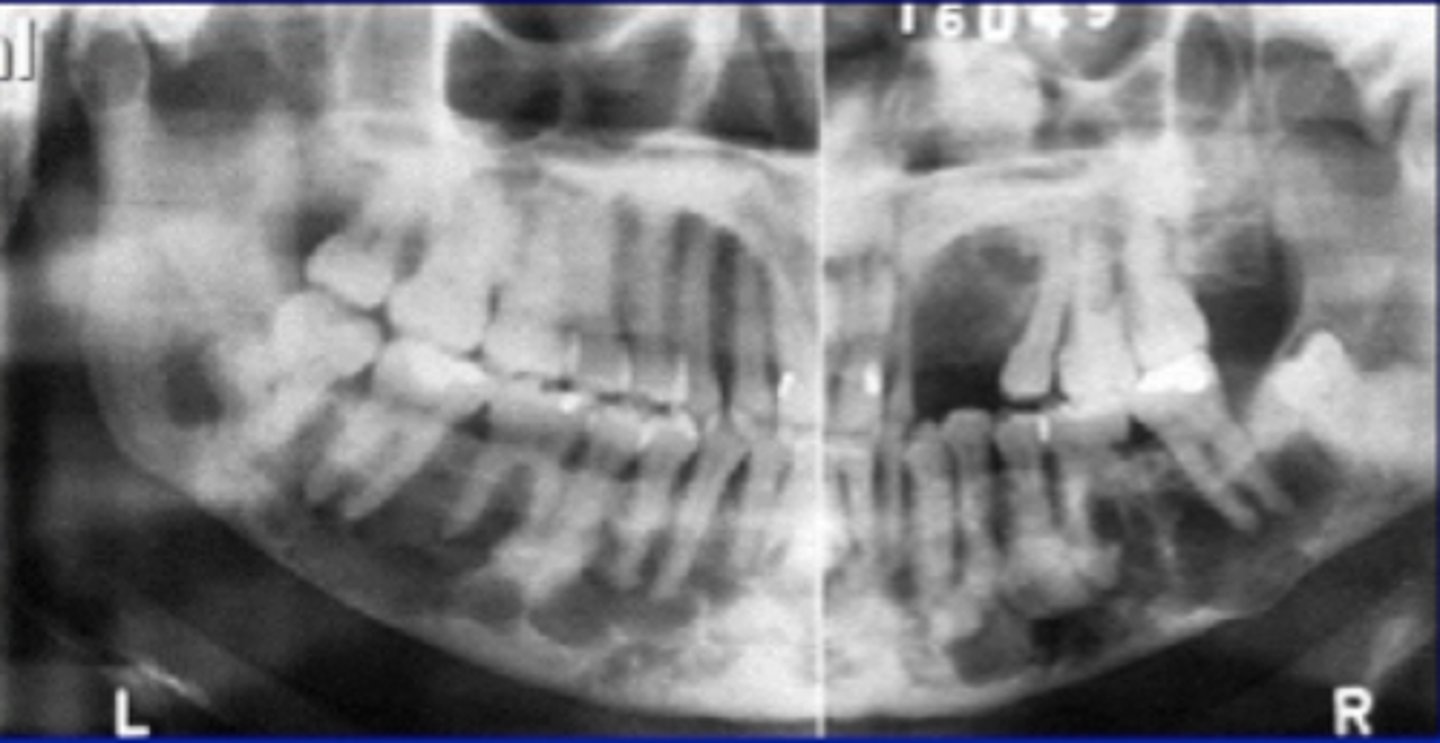

Florid Osseous Dysplasia

widespread form of PCOD.

Normal bone replaced with dense, acellular cemento-ossoeus tissue in background of connective tissue.

poor vascular supply

Clinical Features of Florid Osseous Dysplasia

females

poorly localized

extensive lesions